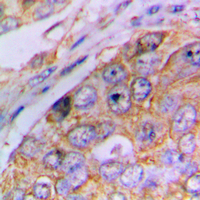

Immunohistochemical analysis of Caspase 4 p20 staining in human lung cancer formalin fixed paraffin embedded tissue section. The section was pre-treated using heat mediated antigen retrieval with sodium citrate buffer (pH 6.0). The section was then incubated with the antibody at room temperature and detected using an HRP conjugated compact polymer system. DAB was used as the chromogen. The section was then counterstained with haematoxylin and mounted with DPX.